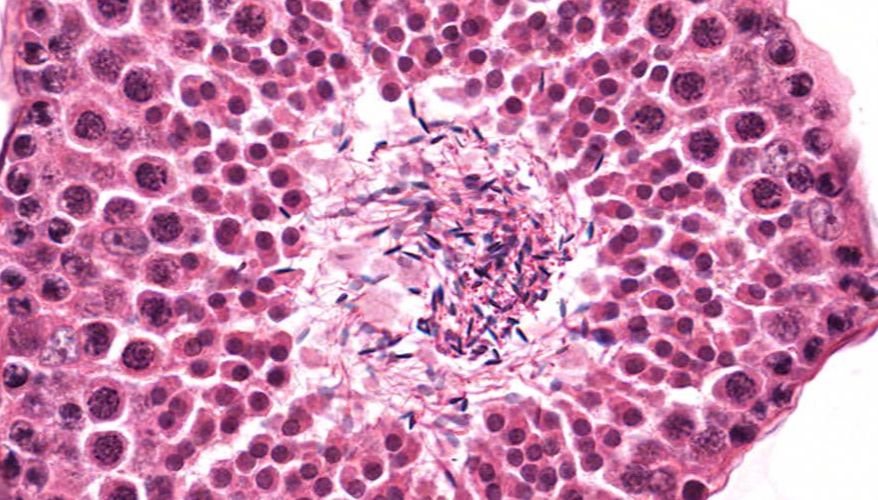

低倍镜:睾丸表面为鞘膜覆盖,其上皮为单层扁平上皮,鞘膜下是一层较厚的致密结缔组织,叫做白膜。白膜在睾丸后缘增厚,形成睾丸纵隔,其内可见不规则的腔隙,即睾丸网。睾丸内可见很多上皮性管道的切面,即生精小管的切面,呈圆形或椭圆形,管壁较厚,由生精上皮及其明显的基膜等组成。高倍镜:着重观察生精小管和其之间的睾丸间质。生精小管主要由生精上皮构成。生精上皮由生精细胞和支持细胞组成。生精细胞是一组细胞,依次自基膜向管腔面排列。

5.生精小管

6.生精上皮

11.精子

13.直精小管

14.睾丸网

15.精子发生